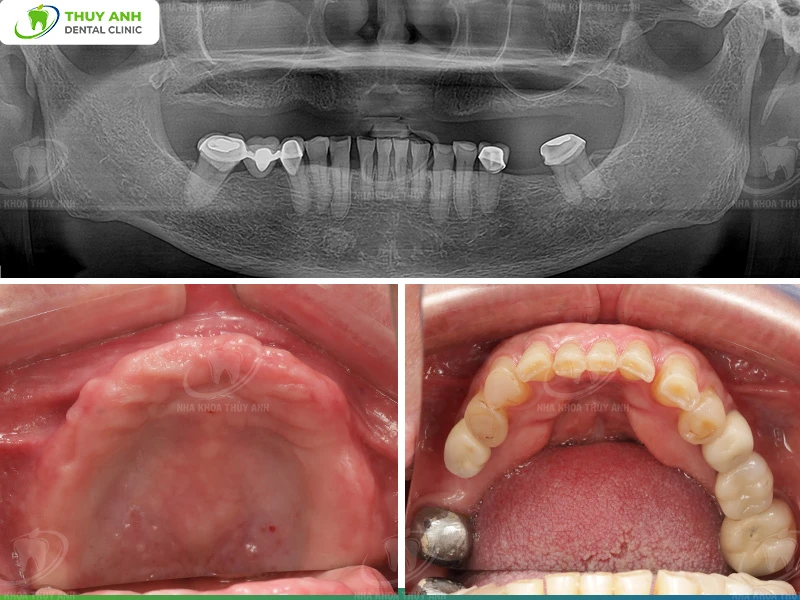

Initial Condition

Carina’s oral condition mainly involved dissatisfaction with her existing dentures:

- Prior to surgery, she was using removable dentures.

- She reported that her old dentures were excessively protrusive. Additionally, the teeth on the dentures were too large for her facial proportions.

- The occlusion was not properly aligned, causing discomfort and difficulty during use.

Carina had planned implant treatment more than five years ago. However, due to the high cost in Melbourne and the long treatment duration (approximately one year), she continued using her old dentures until deciding to seek treatment in Vietnam.